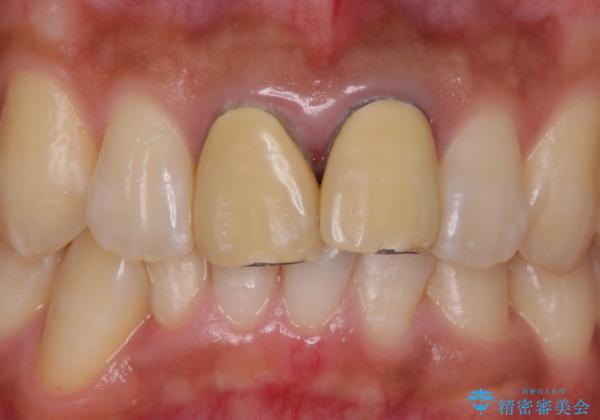

前歯を綺麗にしたい e-maxクラウンでの修復

- 前歯のかぶせ物の変色を主訴に来院された患者様です。

根管治療からのやり直しはご希望されませんでした。

今回はe-maxクラウンで修復していきます。

歯のガタつきも解消することができました。

e-maxクラウンでは仮着ができませんが、今回は一回でご満足いただける修復ができました。